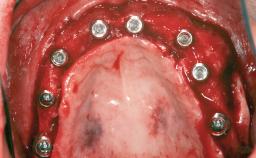

# of Implants 14

Type of Implants Two-Piece

Bone Augmentation Horizontal|Sinus Floor Elevation|Staged|Vertical